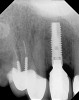

A 53-year-old woman presented with a failing implant in the No. 7 site (Figure 12 and Figure 13). Her desire was to eliminate infection and preserve esthetics. A team effort between the periodontist and restorative dentist to advocate for additional restorative dentistry as well as manage the patient’s expectation of time required was essential. In addition, the patient needed to have realistic expectations of a compromised outcome. Both the restorative dentist and the periodontist informed the patient about the difficulty of achieving this with acceptable esthetic results. Mutual emotional and technical support was required to successfully complete this case, from initial grafting of the defect to placement of anterior restorations (Figure 14 through Figure 23).